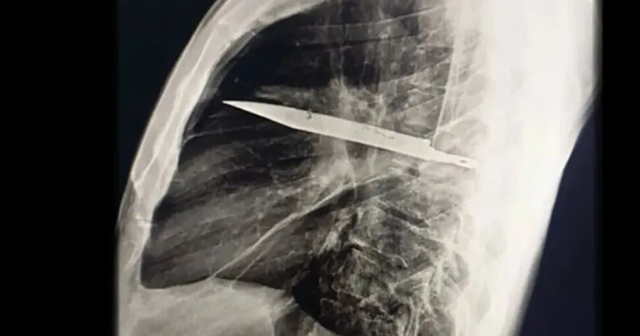

Khi thăm khám, bác sĩ nhận thấy ngực phải của bệnh nhân không nở ra đầy đủ khi hít vào, kèm theo lỗ rò rỉ dịch mủ có mùi hôi. Kết quả chụp X-quang khiến toàn bộ ê-kíp choáng váng: một lưỡi dao lớn gãy nằm gọn trong khoang ngực , kéo dài từ vùng xương bả vai phải đến trước xương sườn.

Phim chụp X-quang ngực của bệnh nhân cho thấy một lưỡi dao lớn găm vào giữa lồng ngực